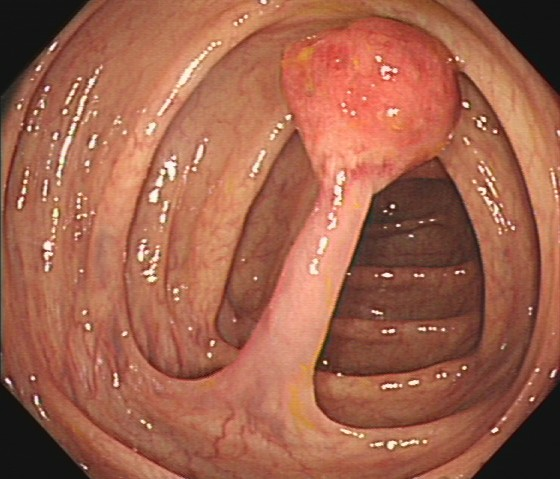

邓先生(54岁,乙状结肠息肉,图3)

肠镜一照,息肉现形!形态各异的大肠息肉,离癌有多远?(图3)

图3

病理诊断:(乙状结肠)管状腺瘤。

解读:这是最常见的腺瘤类型。若未发现高级别瘤变或癌变,属于相对早期的癌前病变。但放任不管,其癌变风险随时间推移而增加。距离癌:潜在风险,癌前病变早期。